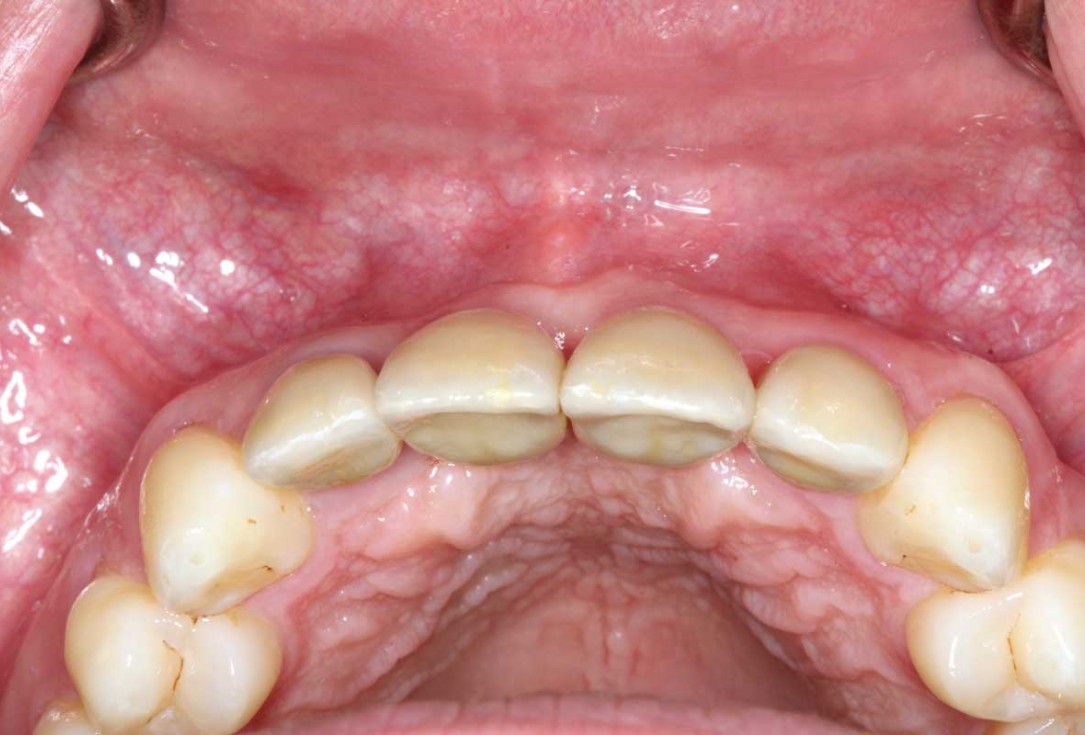

23/26 - Final clinical situation 12 months after augmentation

Ridge augmentation in the maxilla with maxgraft® bonebuilder in the aesthetic zone - Dr. M. Kristensen

24/26 - Final clinical situation 12 months after augmentation